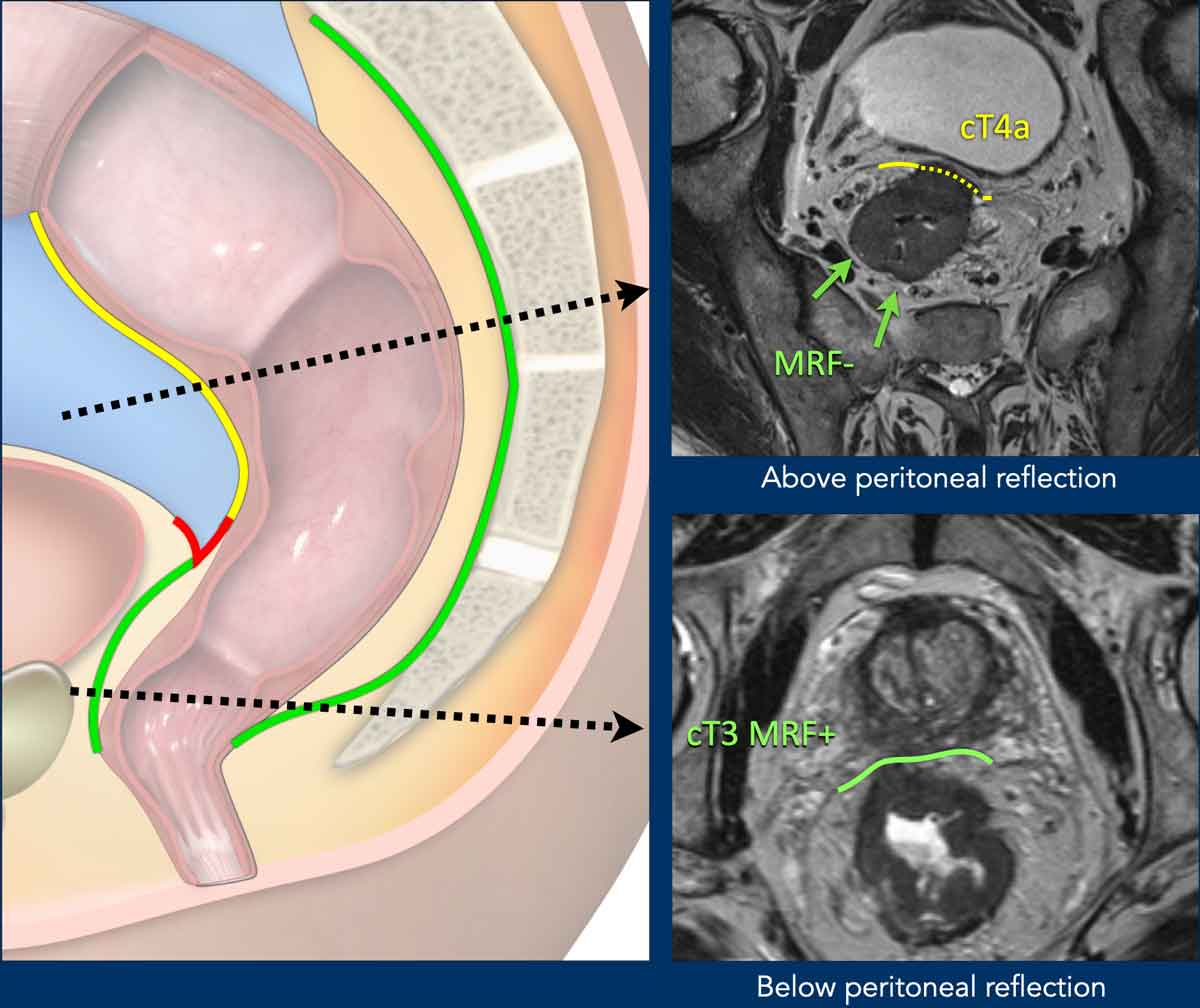

Mesorectal fascia vs. Peritoneum

Anatomical Coverage:

• Low rectum: Fully enclosed by the mesorectal fascia (MRF, green line).

• Middle rectum:

• Posterior/lateral: Covered by MRF

• Anterior: Covered by peritoneum (red line, peritoneal reflection)

• High rectum: Peritoneum extends anteriorly and laterally (yellow line); MRF covers only the dorsal mesorectum.

Clinical Significance:

• MRF invasion: Classified as T3 MRF+

• Peritoneum invasion: Risks peritoneal tumor spread; staged as T4a

T4a Tumor

Anatomical Landmark:

• The anterior peritoneal reflection demarcates the transition between the non-peritonealized and peritonealized rectum.

• Below this reflection, the rectum is entirely extraperitoneal.

MRI Identification:

• On sagittal T2-weighted images, the peritoneal reflection appears as a hypointense, V-shaped thin line (arrow).

• Location:

• Males: Just above the seminal vesicles

• Females: At the level of the cul-de-sac (Douglas pouch)

Staging Implication:

• Anterior invasion of the peritoneal reflection or peritoneum defines T4a disease.

Pitfall: Distinguishing MRF vs. Peritoneal Invasion in Anterior Tumors

Key Principle:

• Anteriorly, MRF invasion can only occur in tumors below the peritoneal reflection, reported as T3 MRF+

Anterior tumors above the peritoneal reflection that invade the peritoneum should be reported as T4a MRF

• Posteriorly, the MRF extends above the level of the peritoneal reflection. Simultaneous involvement of the MRF (posteriorly) and peritoneum (anteriorly) can occur, which should be reported as T4a MRF+

Image Examples

cT4a MRF– (Upper Image):

• Upper rectal tumor, above the peritoneal reflection

• Peritoneal involvement (dashed yellow line)

• No MRF involvement

cT3 MRF+ (Lower Image):

• Distal rectal tumor, below the peritoneal reflection

• Anterior MRF involvement (green line)

• No peritoneal involvement